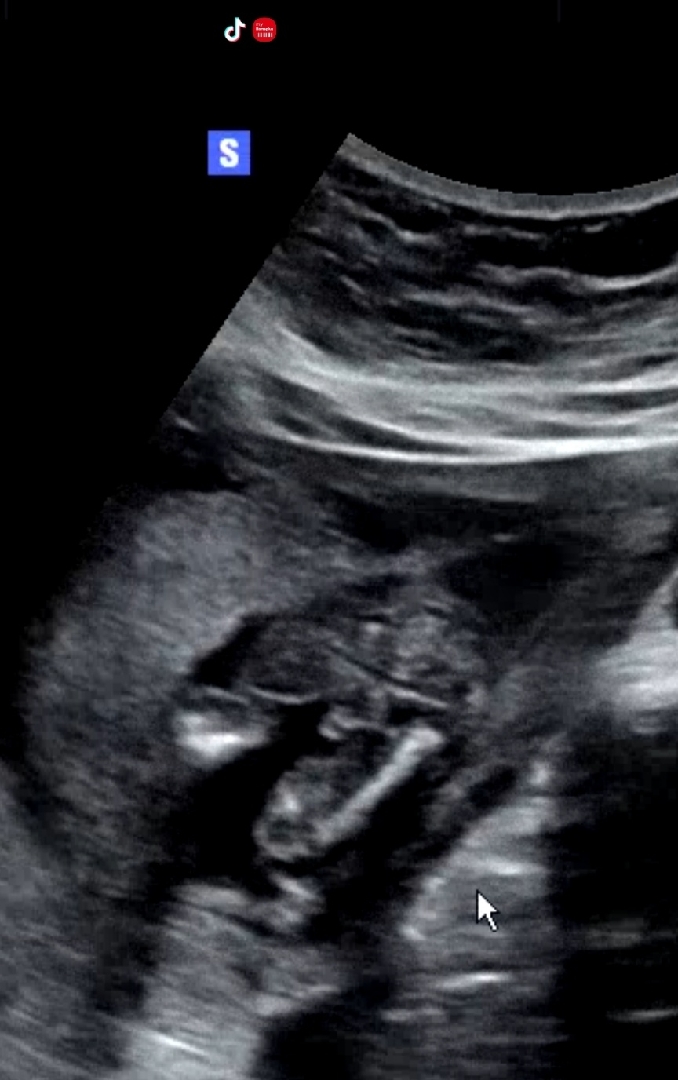

오늘 16주2일 기형아2차 하구왔어용 애기가 배꼽에 있어서 잘안보여준다 하셨는데 고추같다 하셨는데, 아들일까용??